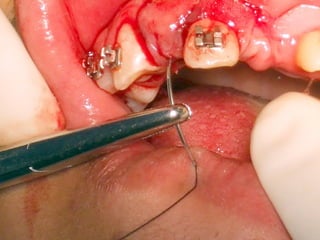

Mini-implantes para apoyo de fuerzas ortodóncicas

Mini-implantes para apoyode fuerzas ortodóncicas